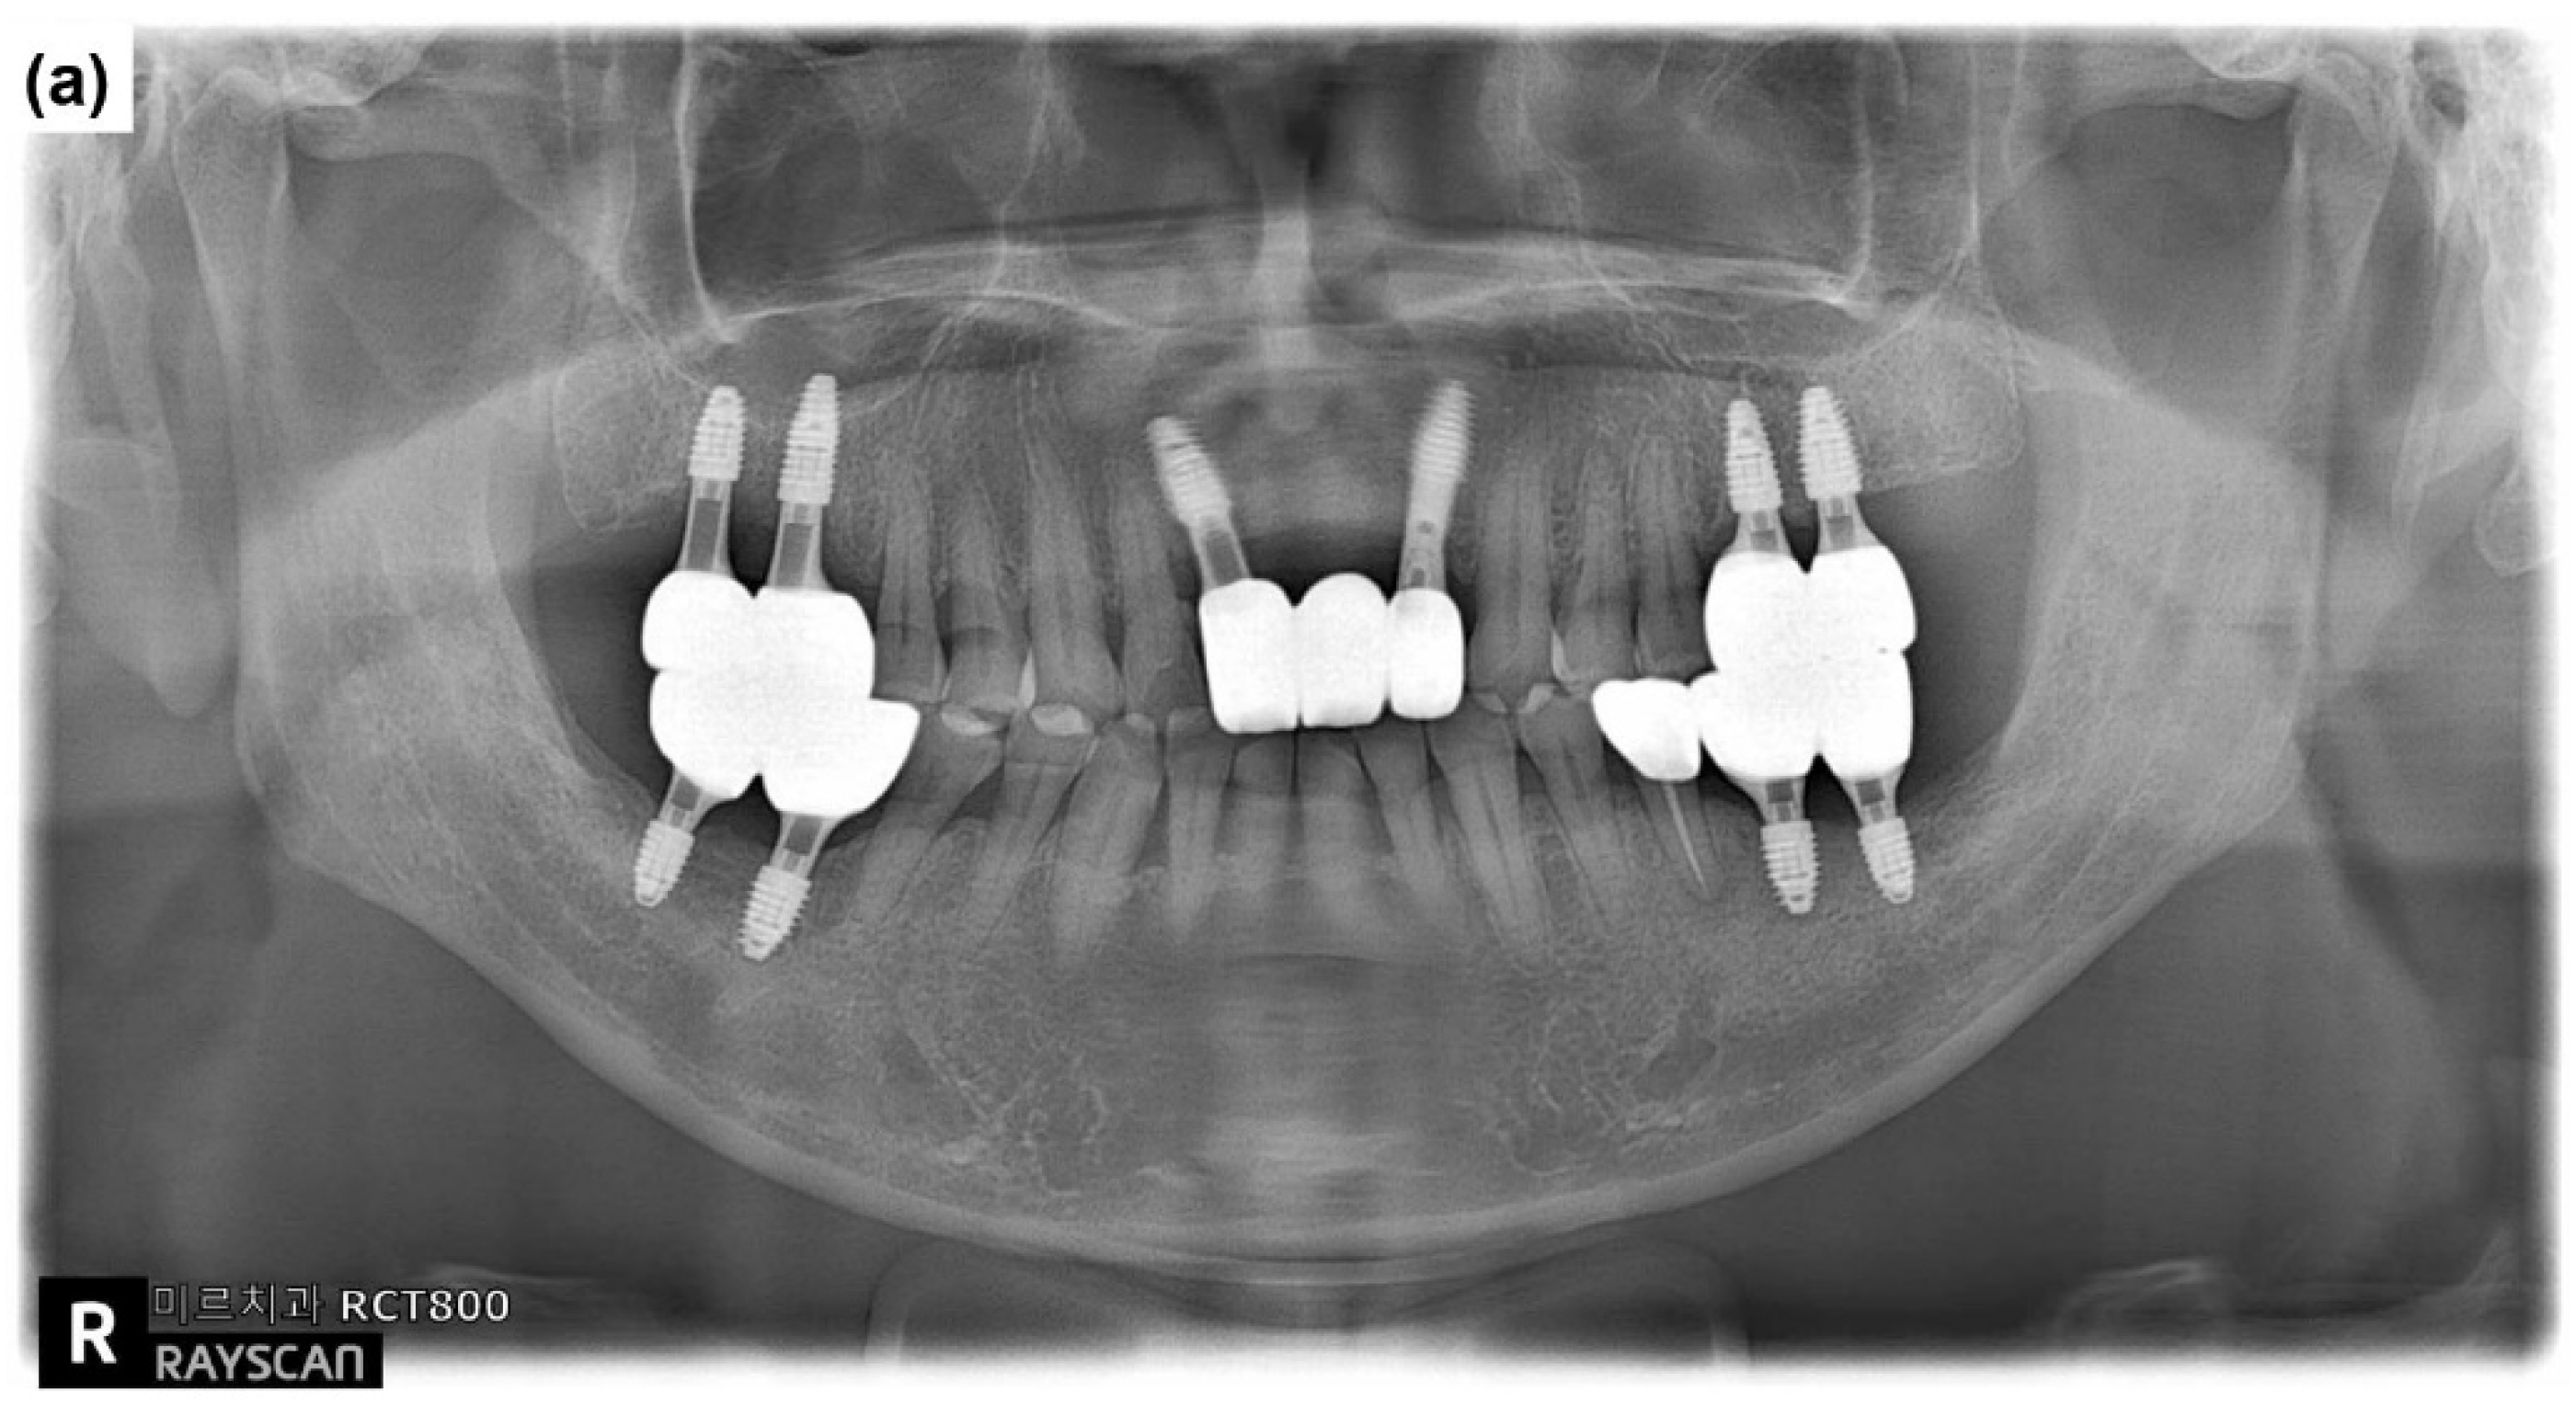

3. Results and Discussion